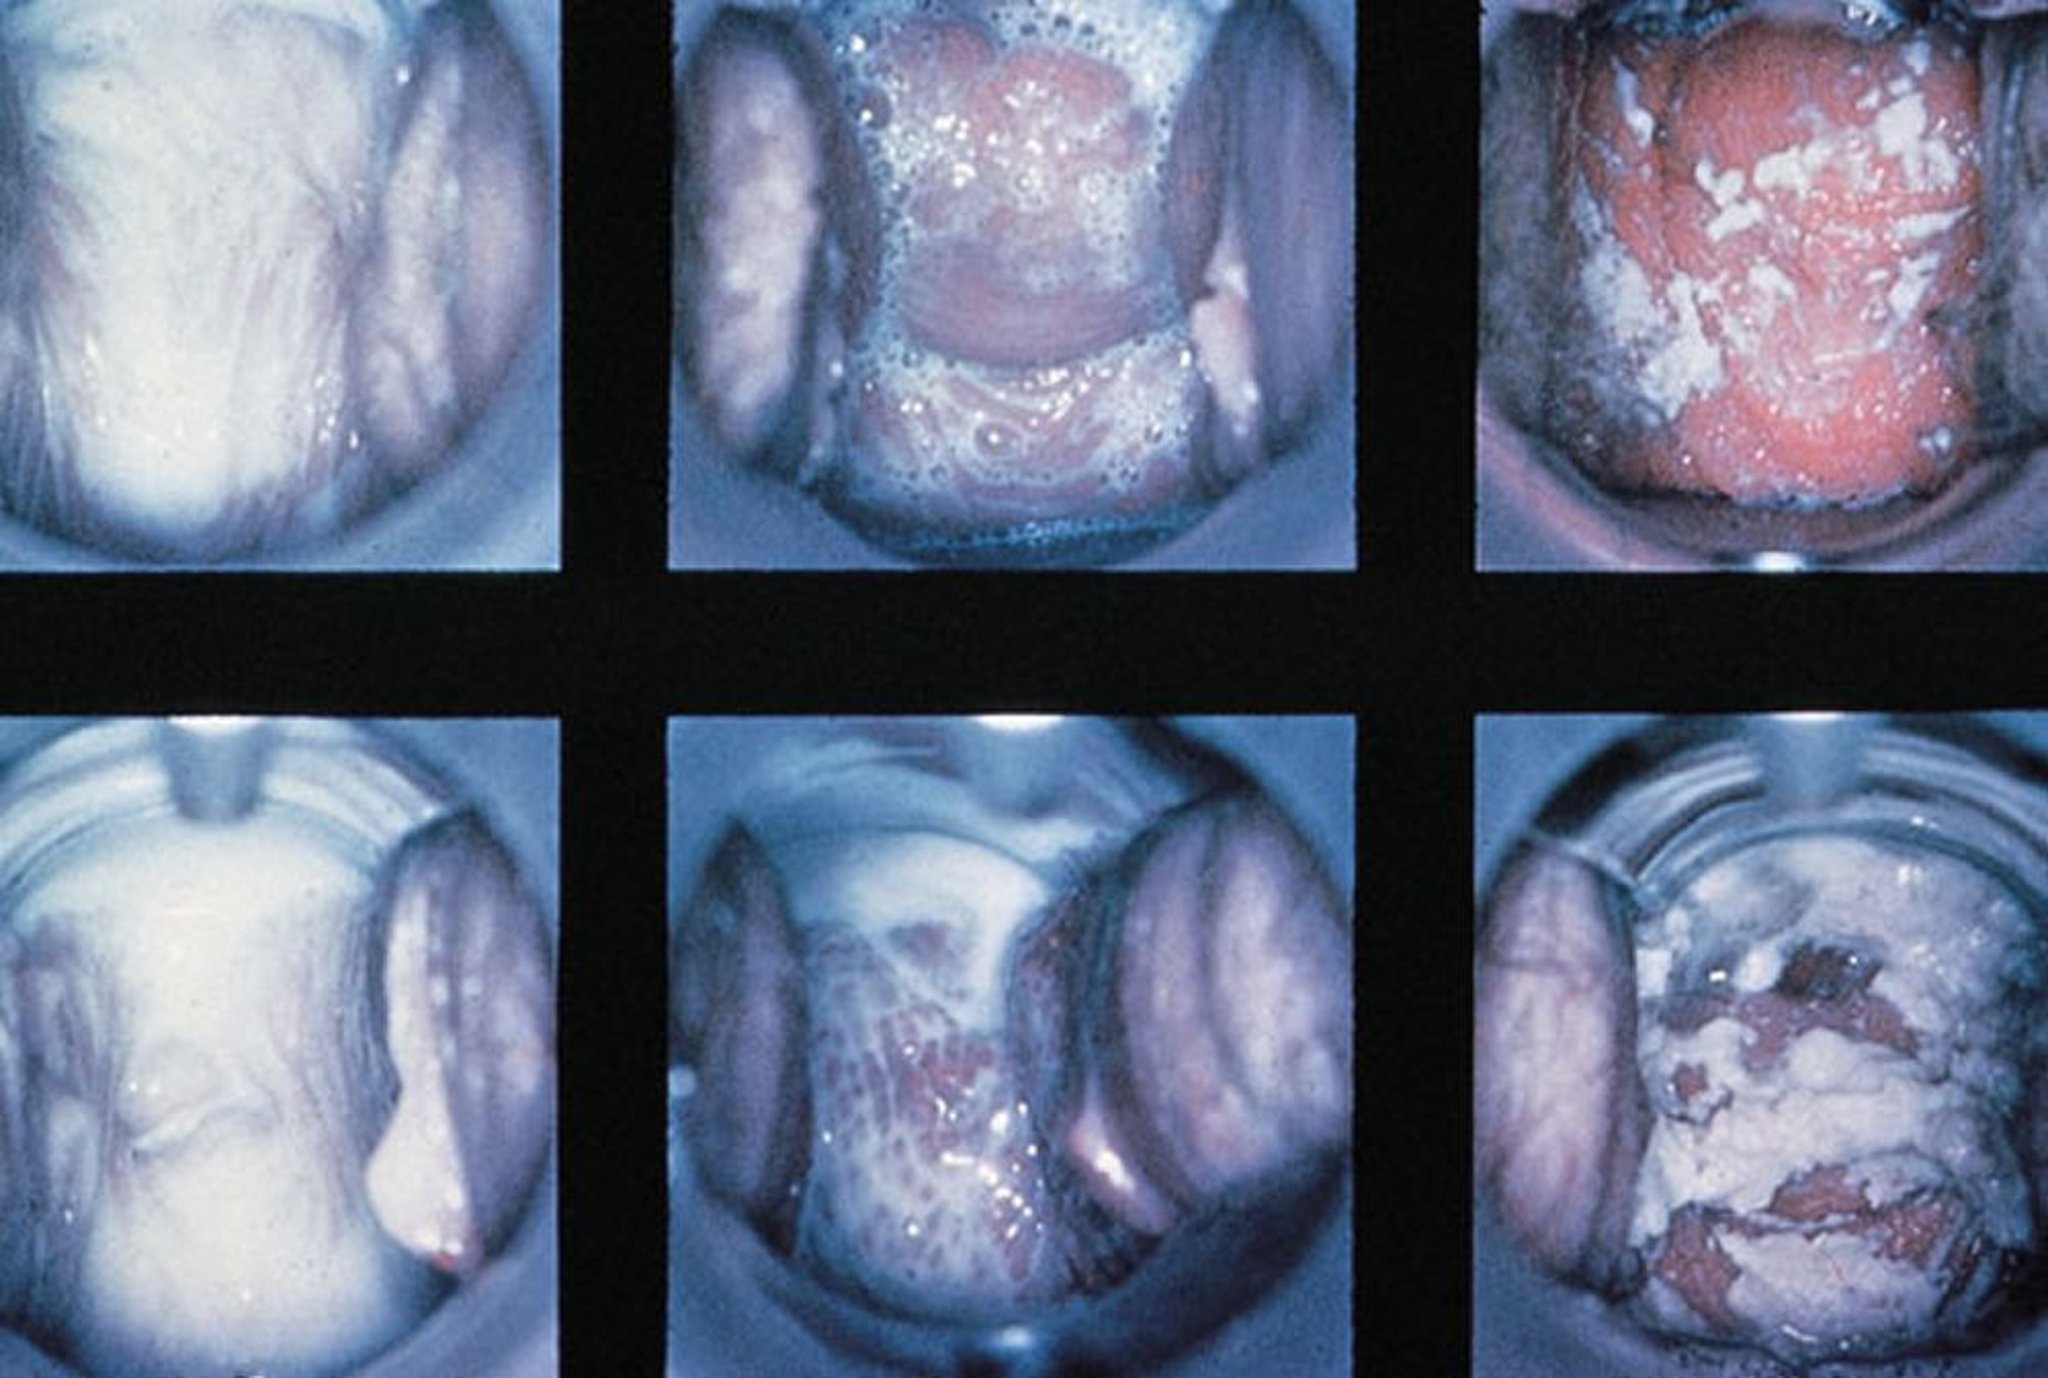

Spekulumuntersuchung bei Vaginitis

Abgebildet sind normale Befunde, Trichomonaden-Vaginitis mit schaumigem Ausfluss und Candida-Vaginitis mit dickem, weißem Ausfluss (von links nach rechts).